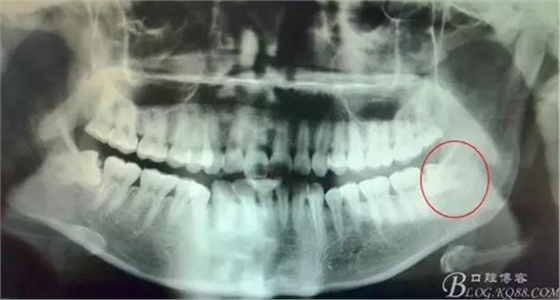

圖1.全景片檢查:38水平位、雙根、分叉大。